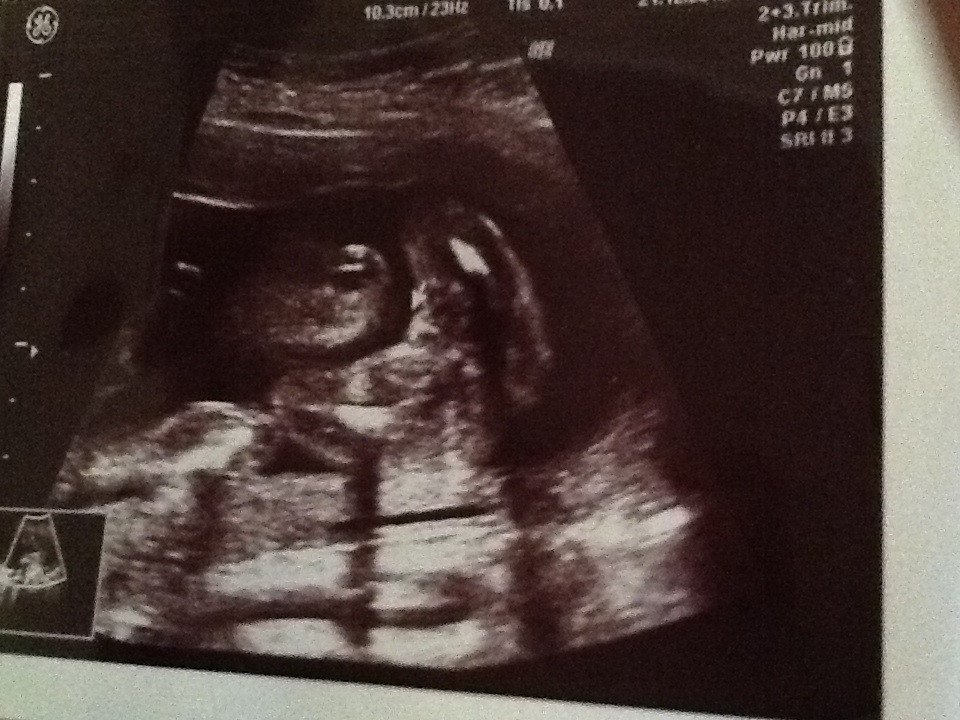

We were told "maybe girl" in 20 weeks 5 days u/s. What do you ladies think of the pic? I'm scared to buy anything or tell anyone if it turns out the baby is boy after all.Attachment 7451

Yes girl

Looks girl to me

I can see why they said "maybe" though I'd say most likely a girl.

I'm totally gonna say GIRL! :cheer:

Girl!!

Looks like a girl. Congrats!